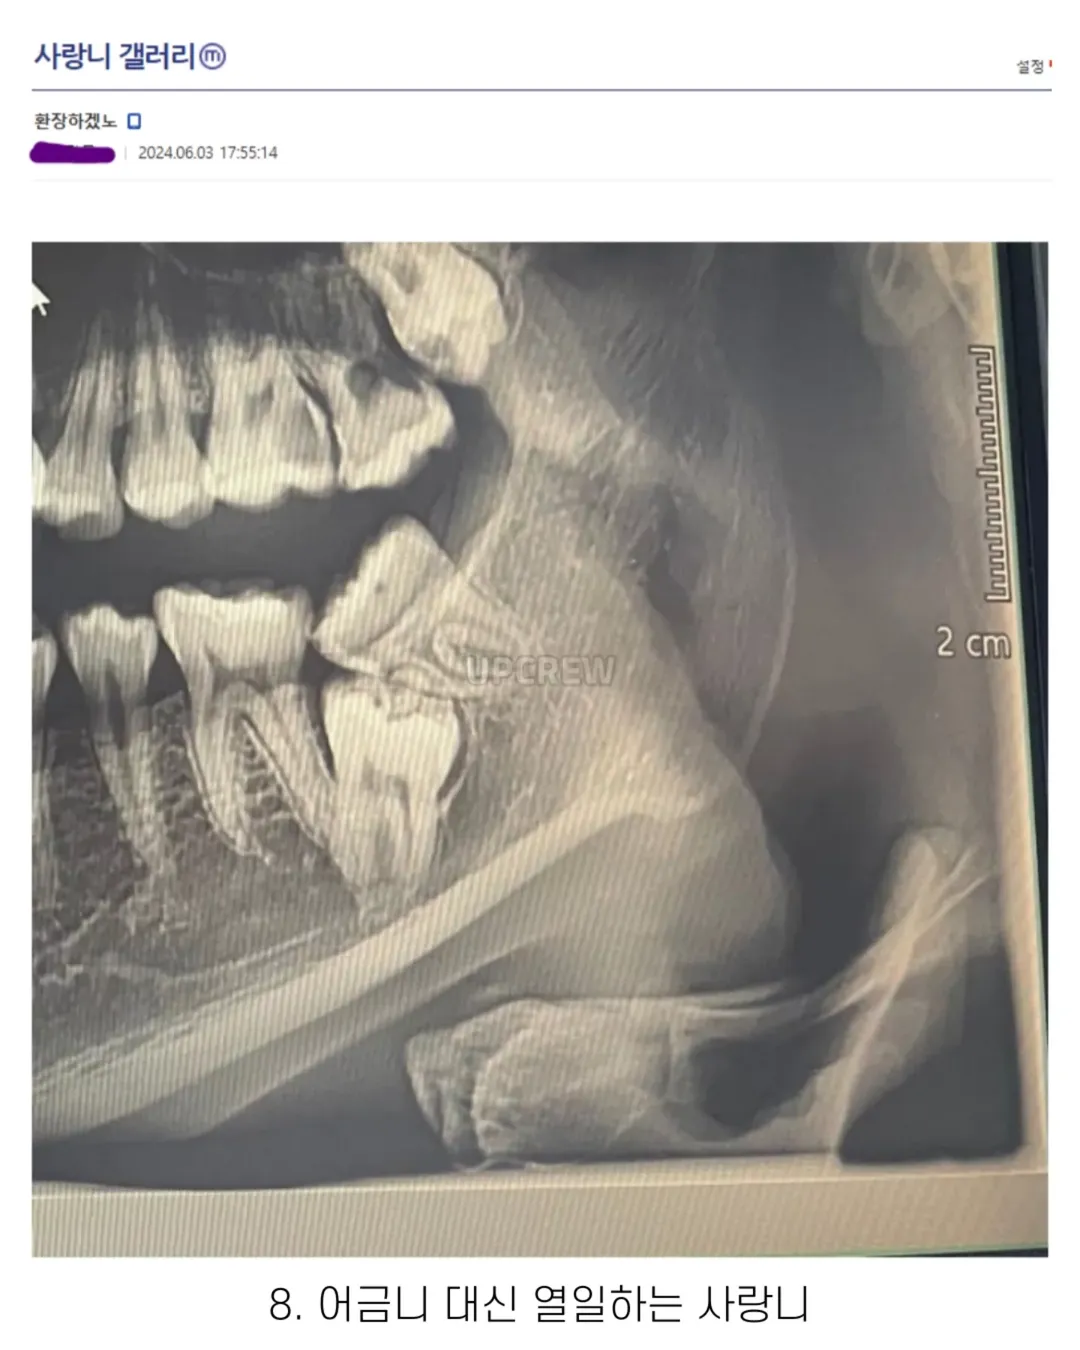

사랑니 갤러리의 특이한 사랑니들 (약혐 주의)

와 8번은 어금니까지 둘 다 뽑나...???